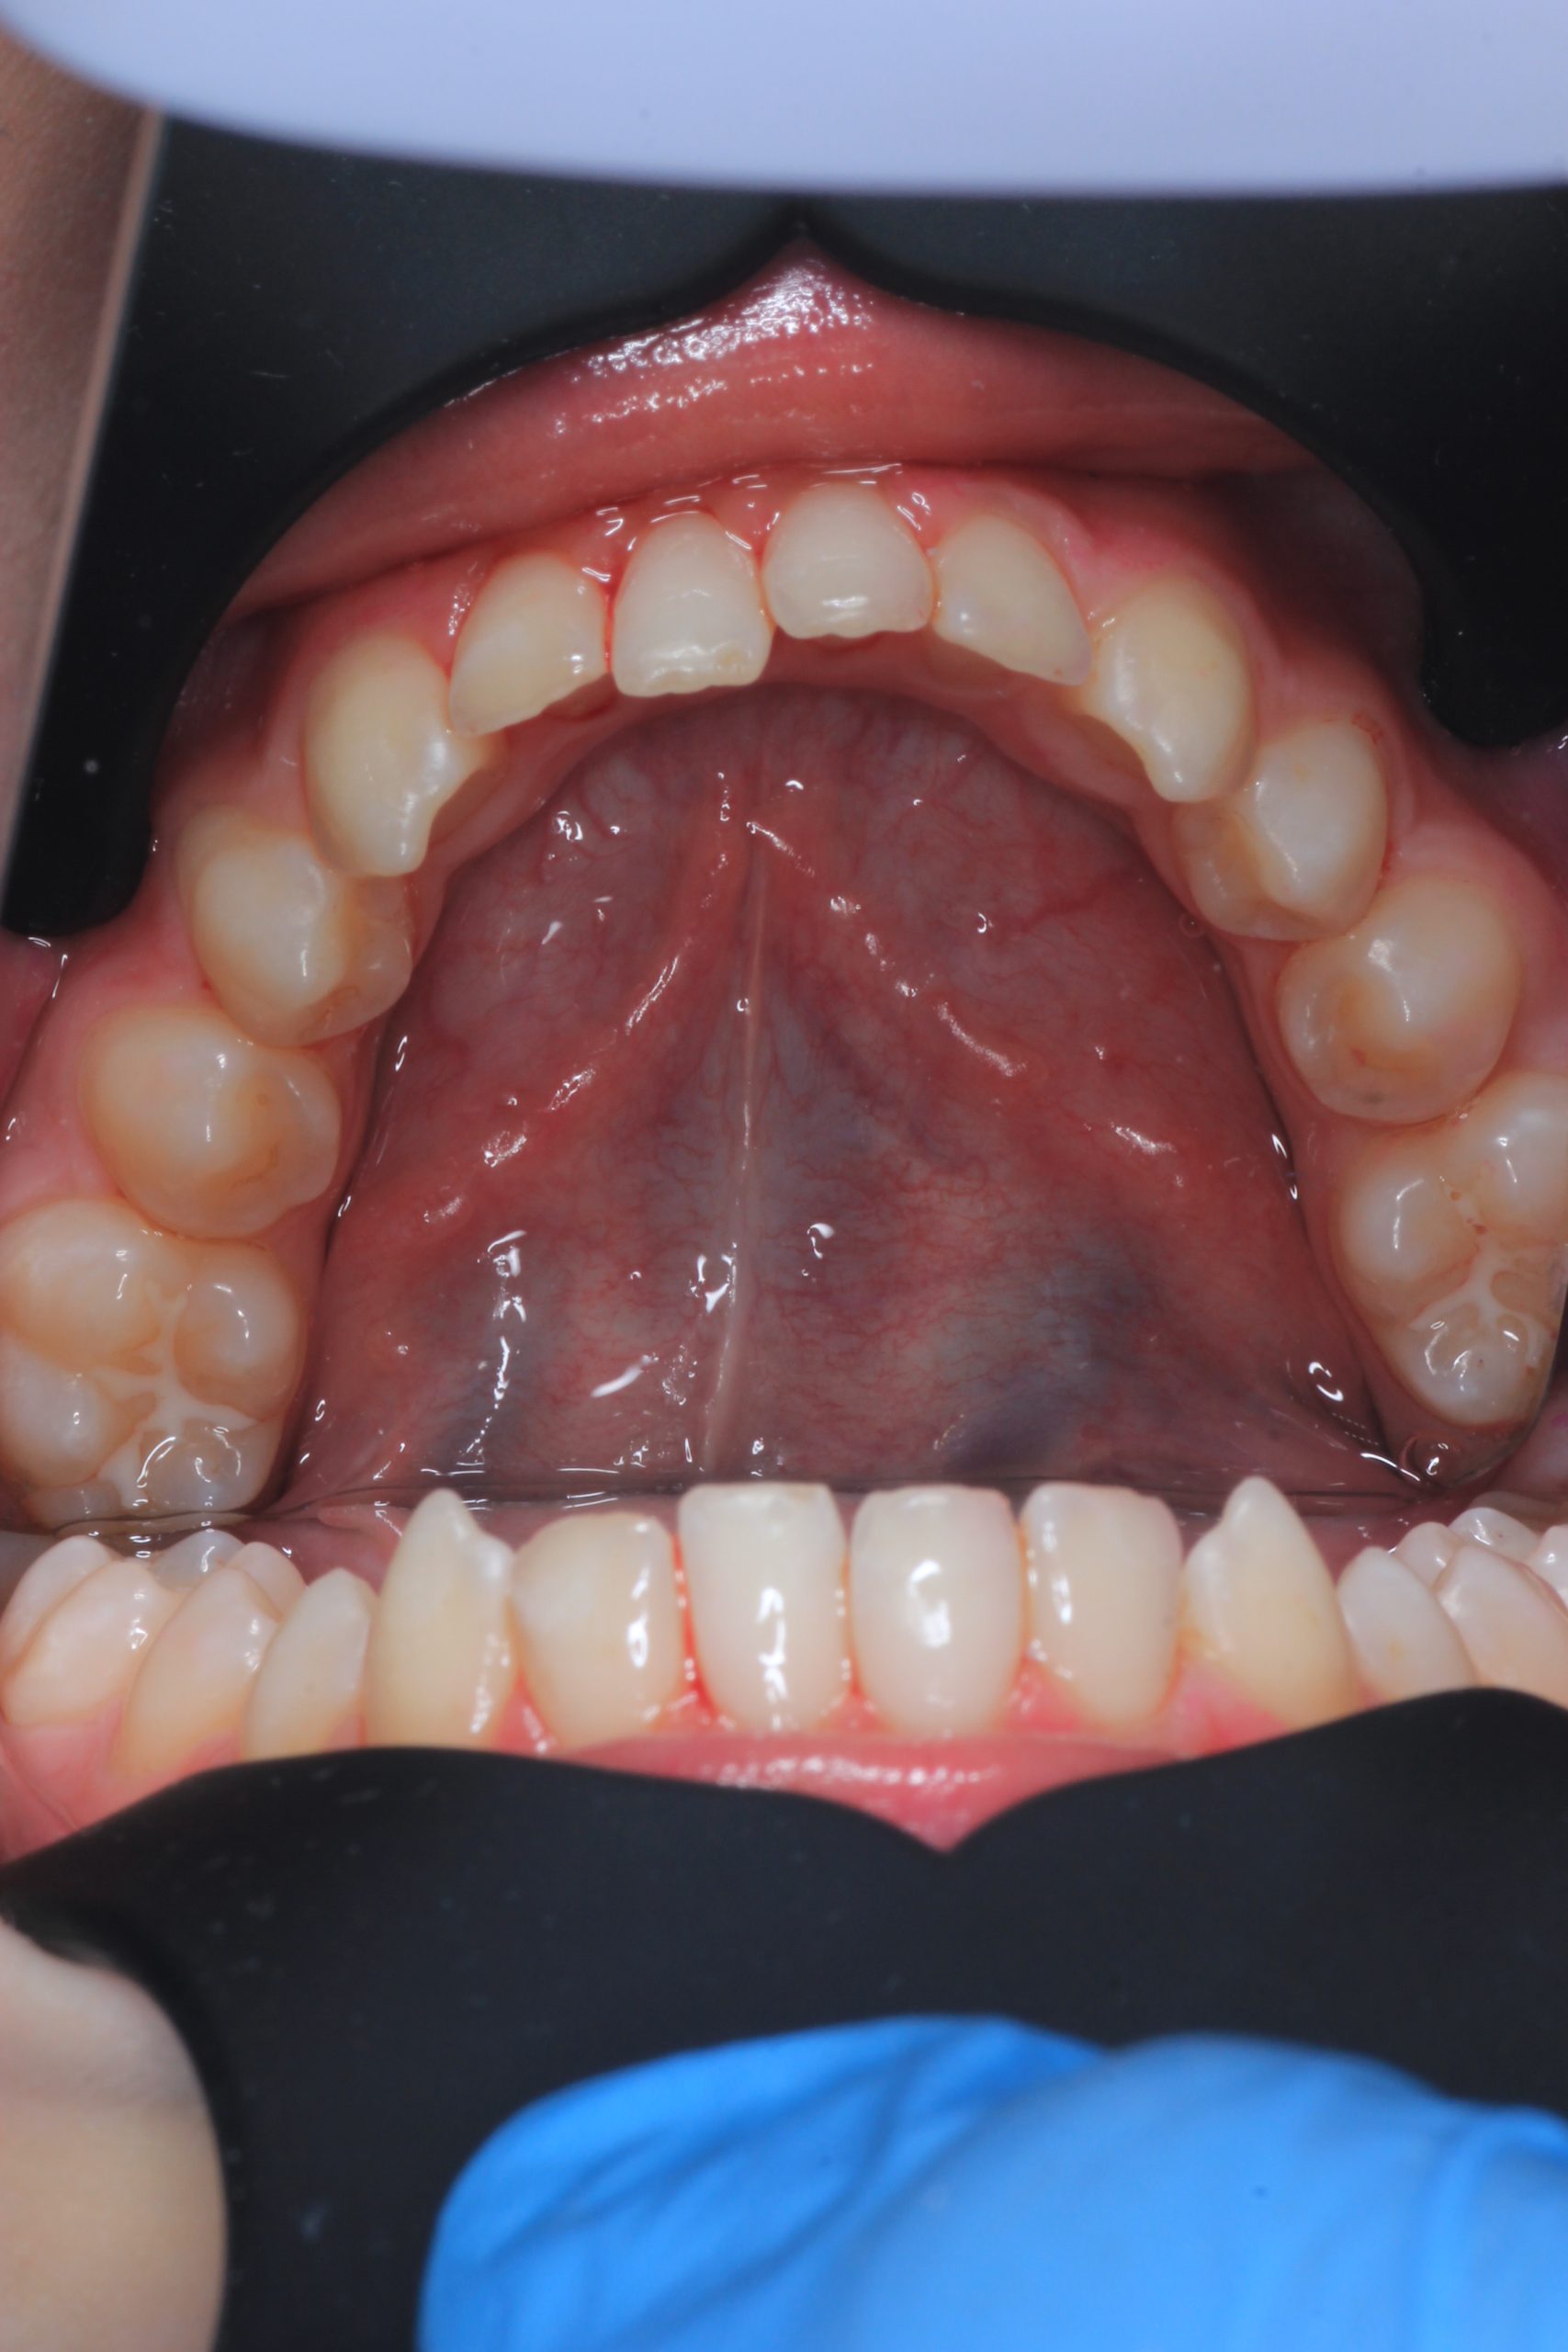

We examine the condition of teeth, gums, and bite. - Plaque Disclosure with Special Indicators

Areas that weren’t cleaned well appear purple. The darker the shade, the older the plaque. This helps both kids and parents understand where brushing needs to improve. - Brushing Training & Home Care Tools Selection